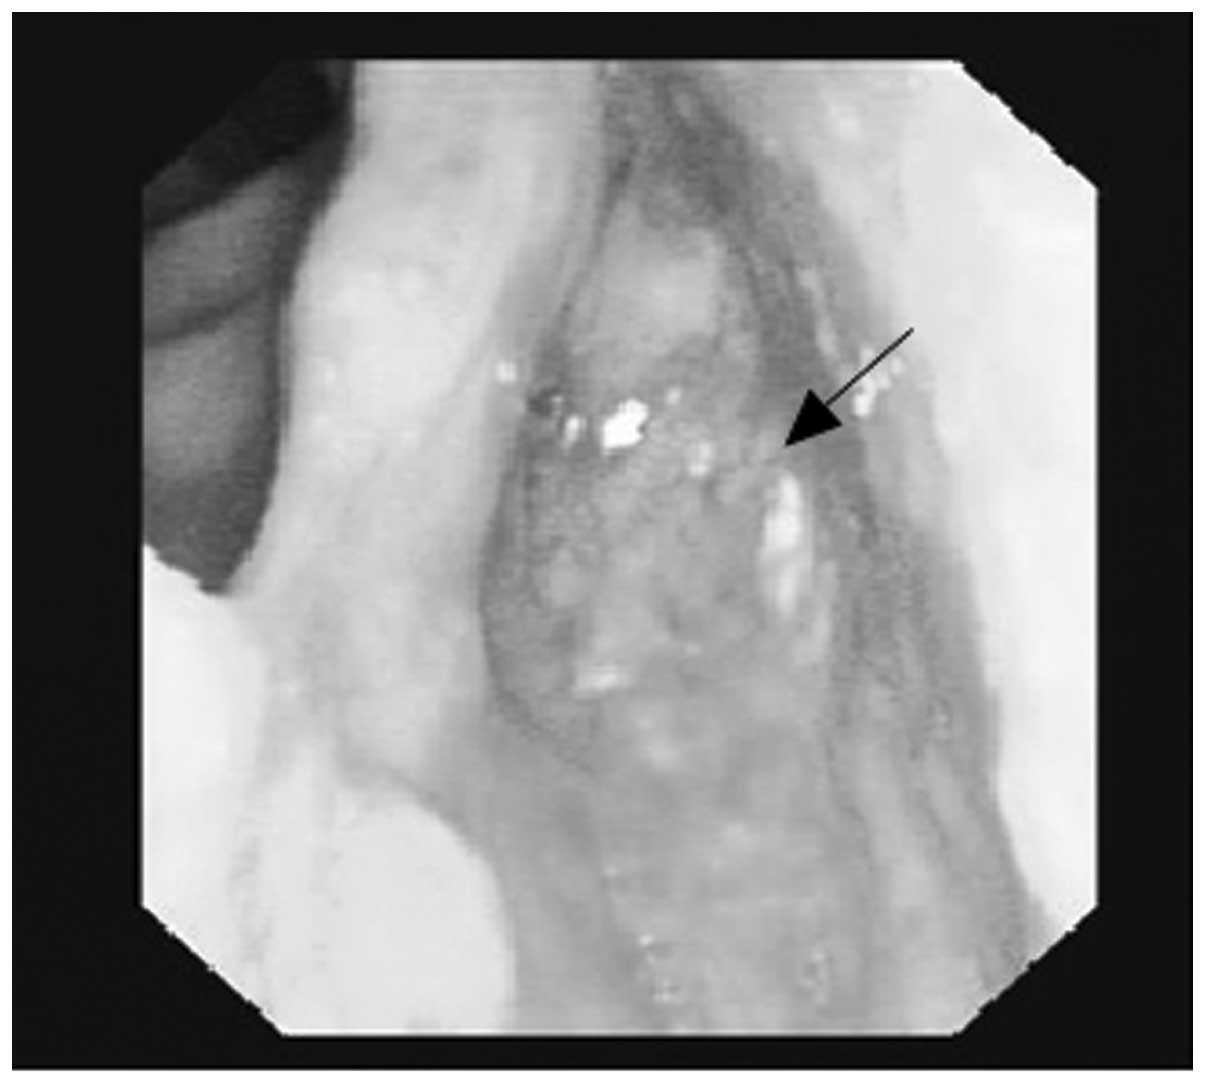

A 55-year-old male was admitted to the Department of Otolaryngology and Head and Neck Surgery, Sir Run Run Shaw Hospital, Medical College of Zhejiang University (Hangzhou, China) complaining of a mass on the left side of the neck, which had been present for six months. The patient reported that the mass had increased rapidly over the two preceding months. The patient stated there was no tenderness or paresthesia, however, the mass had been punctured and pus had been extracted at the Jiangshan Beilin Hospital (Jiangshan, China). An endoscopy revealed a 1.5-cm submucosal mass in the left pyriform sinus, which extended to the lateral wall (Fig. 1). The posterior pharyngeal wall, vocal cords, subglottic region and the base of the tongue appeared to be healthy. Computed tomographic (CT) examinations demonstrated a soft tissue mass in the left pyriform sinus and a 4.4×4.1-cm lesion, which was not well defined from the surrounding healthy soft tissue on the left side of the neck (Fig. 2).